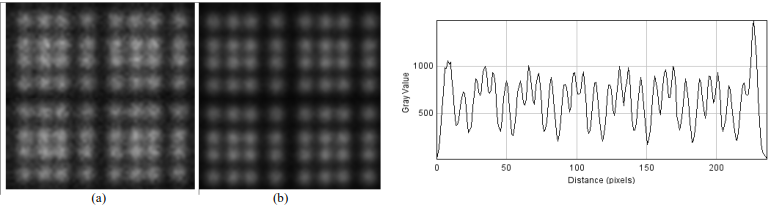

| ABSTRACT | When multiple pinholes are used to acquire SPECT projection data, there may be regions on the detectors where data from two or more pinholes overlap. Such “multiplexing” of projection data can cause artifacts and/or increased noise in reconstructed SPECT images, depending on the exact acquisition geometry. We previously described a modified MLEM algorithm that alternates between (i) estimating the separated projection data that would be obtained through each individual pinhole (i.e., demultiplexed data), based on the current MLEM iteration’s image, and (ii) reconstructing the SPECT image by MLEM, but assuming that the demultiplexed data estimates are the actual measured data. The modified MLEM algorithm was first tested with data simulated for a stationary 39pinhole collimator tube, and more recently with Tc99m phantom data acquired from three vials of different sizes on a 6pinhole, tripledetector SPECT camera. |

Lack of spatial resolution is a major drawback in small-animal SPECT imaging, particularly when parallel hole collimators are employed. This work evaluates the feasibility of enhancing the spatial resolution of a small-animal SPECT scanner by applying an approach based on a super-resolution technique combined with dedicated hardware.

En este trabajo se evalúa la posibilidad de aplicar un enfoque basado en técnicas de super-resolución y hardware dedicado para la mejora de la resolución espacial de un tomógrafo SPECT de animales de laboratorio. El sistema de detección del aparato está basado en cristales de centelleo pixelados de NaI(Tl), tubos fotomultiplicadores sensibles a posición y colimadores de agujeros paralelos.